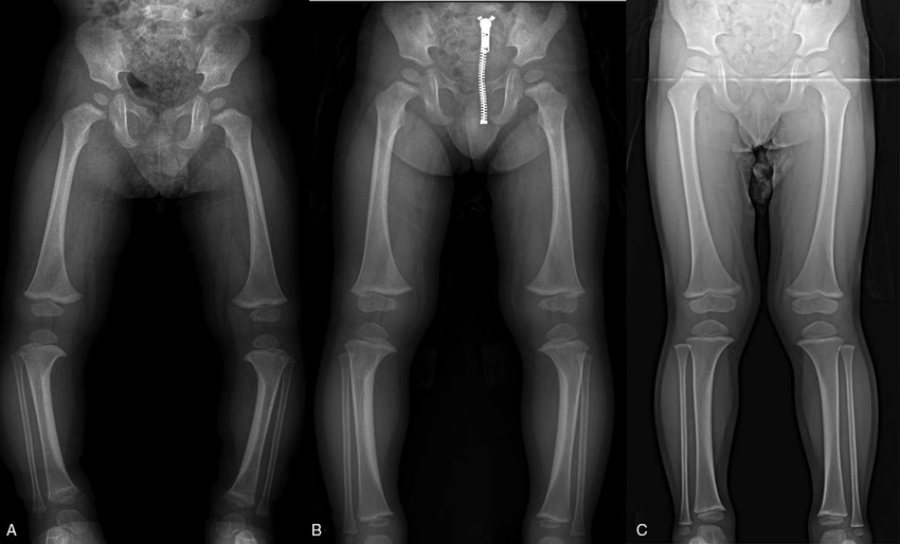

در مواردی که انحراف پای پرانتزی بسیار شدید است، به درمانهای غیرجراحی پاسخ نمیدهد یا ناشی از یک بیماری زمینهای خاص است، جراحی به عنوان مؤثرترین راه حل در نظر گرفته میشود. جراحیهای رایج برای اصلاح پای پرانتزی شامل استئوتومی (Osteotomy) و رشد هدایتشده (Guided Growth) هستند. استئوتومی که برای بزرگسالان و نوجوانان با رشد کامل اسکلتی مناسب است، شامل برش و تغییر شکل استخوان ساق پا یا ران برای همراستایی صحیح آن است. پس از جراحی، بیمار باید از گچ یا بریس استفاده کند و دوره نقاهت چند ماهه را طی کند.

روش رشد هدایتشده، یک تکنیک جراحی کمتر تهاجمی است که به طور اختصاصی برای کودکان و نوجوانان در حال رشد استفاده میشود. در این روش، پزشک صفحات فلزی کوچکی را در نزدیکی زانو، در سمتی که رشد سریعتر است، قرار میدهد. این صفحات به صورت موقت رشد آن بخش از استخوان را کند میکنند و به سمت دیگر اجازه میدهند تا رشد کرده و به تدریج انحراف را اصلاح کند. این فرآیند ممکن است چندین ماه تا یک یا دو سال طول بکشد تا بهبودی کامل حاصل شود، اما به دلیل ماهیت کمتر تهاجمی، دوره بهبودی پس از برداشتن صفحات فلزی کوتاهتر است. به هر حال، هر دو روش جراحی، زمانبر بوده و نیاز به پیگیری و مراقبتهای پس از عمل دارند.